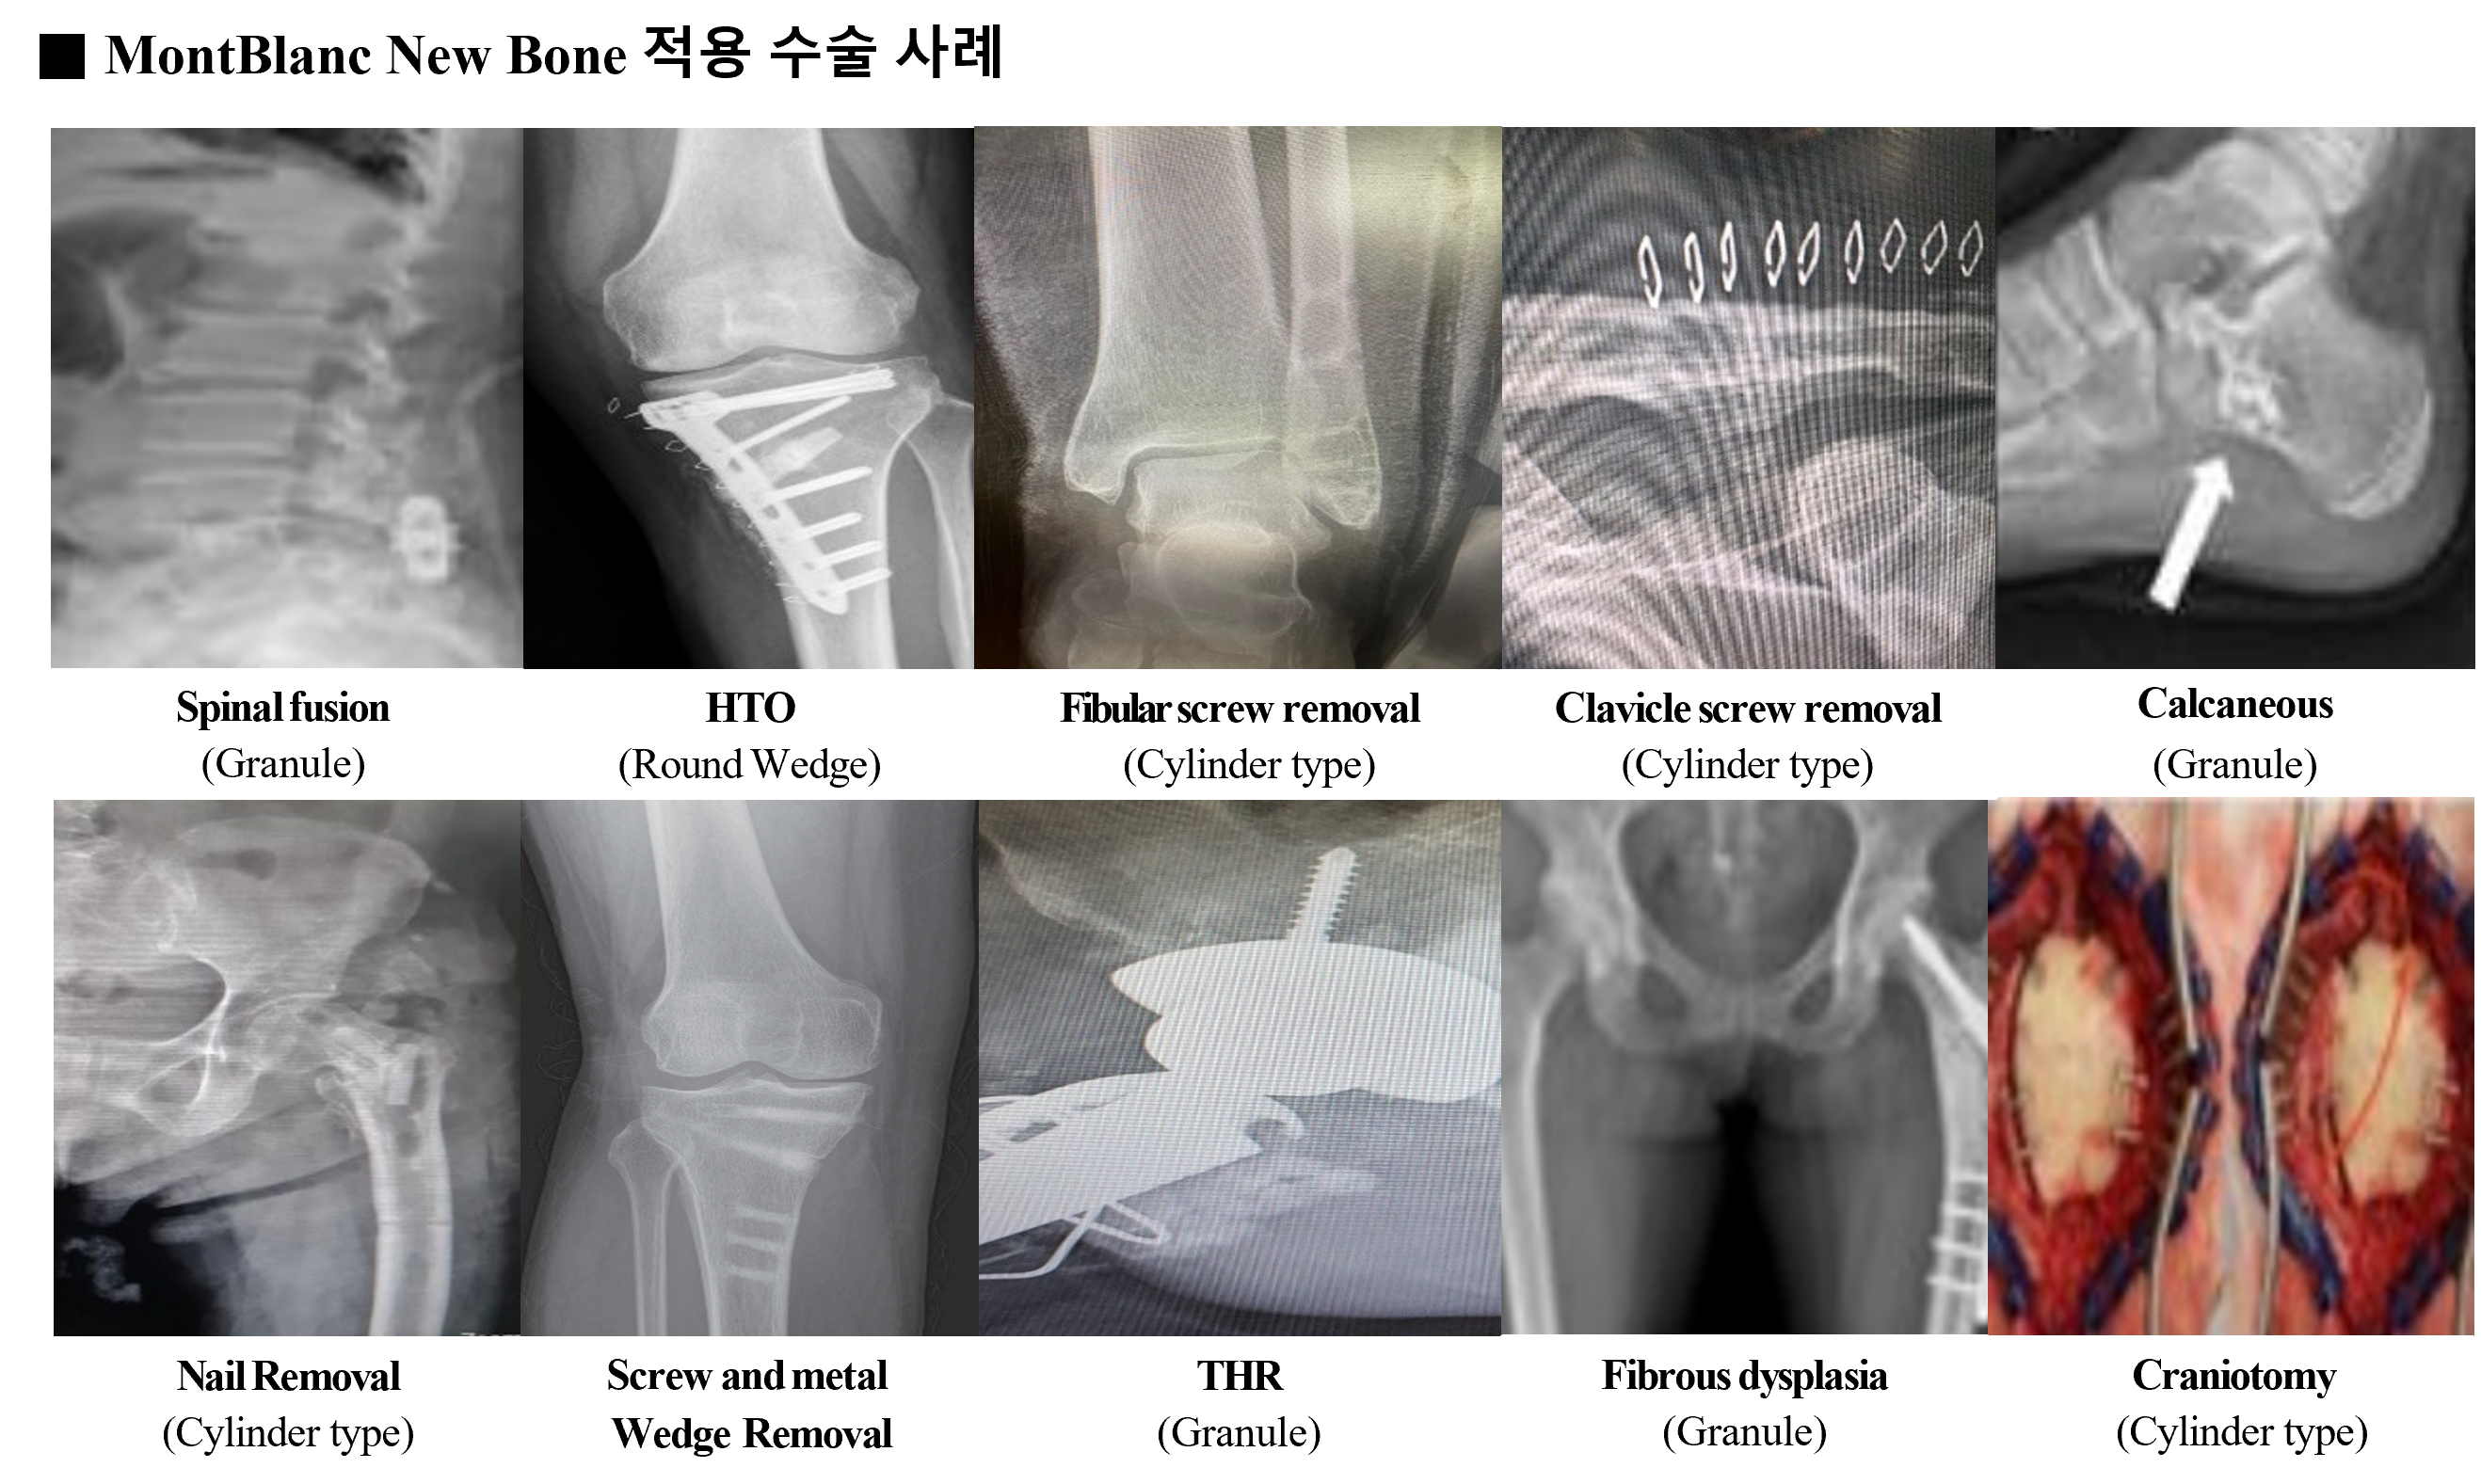

MontBlanc New Bone

베타-트리칼슘포스페이트(β-tricalciumphosphate, TCP) 100% 원재료

세계최초 특허 등록 기술이 집약된 혁신적인 골이식재

월등한 Blood supply를 통해 Scaffold 와 Healing 기능을 완벽히 충족

임상학적으로 증명된 우수한 생체 친화성 합성 재료 이식용 뼈